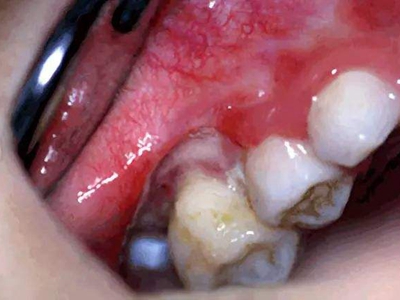

急性坏死性溃疡性龈炎起病急,病程短,常为数天至1-2周,以龈乳头和龈缘的坏死为其特征性损害,尤以下前牙多见,初起时龈乳头充血水肿,个别龈乳头顶端可发生坏死性溃疡,上覆有灰白色坏死物,中央凹下如火山口状。龈缘如虫蚀状,坏死区出现灰褐色假膜,擦去后可见出血创面。龈乳头被破坏后与龈缘成一直线,如刀切状。病损一般不波及附着龈,患处牙龈极易出血,疼痛明显并有腐败性口臭。